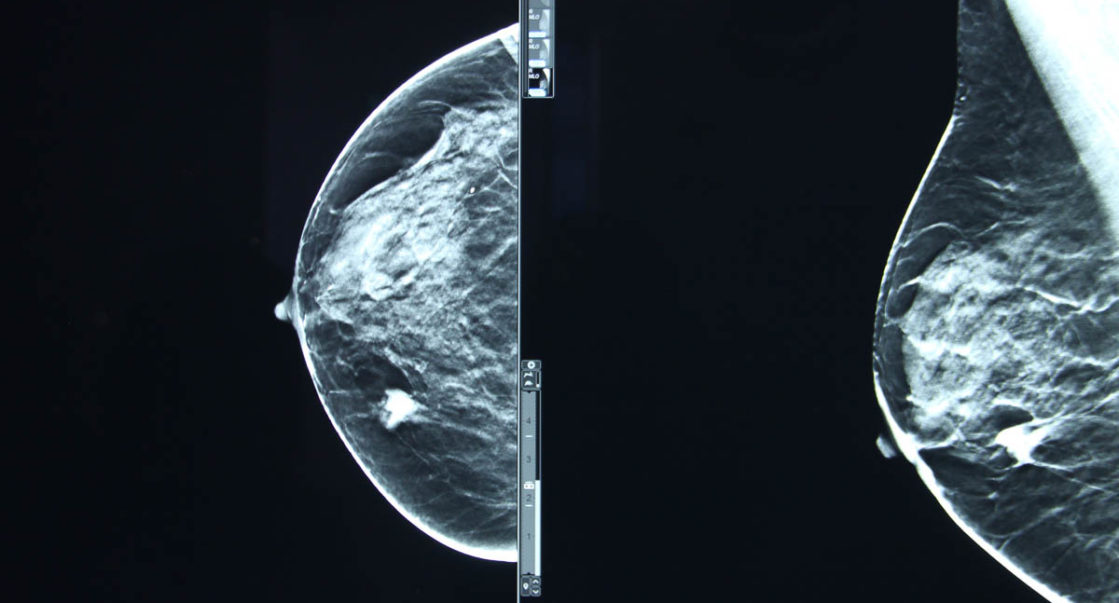

L’évènement qui s’est déroulé ces 26 et 27 octobre, a abordé plusieurs thématiques, dont le cancer broncho-pulmonaire non à petites cellules, l’échinococcose kystique ainsi que l’actualité dans la prise en charge du cancer du sein.

De son côté, et dans une déclaration à Radio M, la présidente de la société algérienne d’oncologie thoracique, Pr Aziza Fissah a souligné que l’évènement “a couplé deux pathologies qui sont fréquentes en Algérie : le cancer du thorax et le cancer du sein, ce dernier qui touche beaucoup les jeunes femmes dès 40 ans “.

“Il y a beaucoup de choses à dire sur le cancer du sein, mais le plus important et c’est le thème qu’on a choisi aujourd’hui, celui de ce type de cancer chez la femme de jeune âge, parce qu’il est souvent familial et de facteur héréditaire et génétique” ajoute Pr Fissah tout en insistant : “maintenant, on va essayer de dépister ces cancers chez les autres membres de la famille pour pouvoir faire de la prévention”.

Concernant les chiffres de cette année sur les femmes atteintes du cancer du sein, Pr Fissah a affirmé que le nombre de 15000 nouveaux cas par an est intriguant : “oui, c’est intrigant, le cancer du sein chez la femme fait de véritables ravages, on a une prévalence plus importante que dans d’autres pays surtout chez les femmes de jeune âge”.